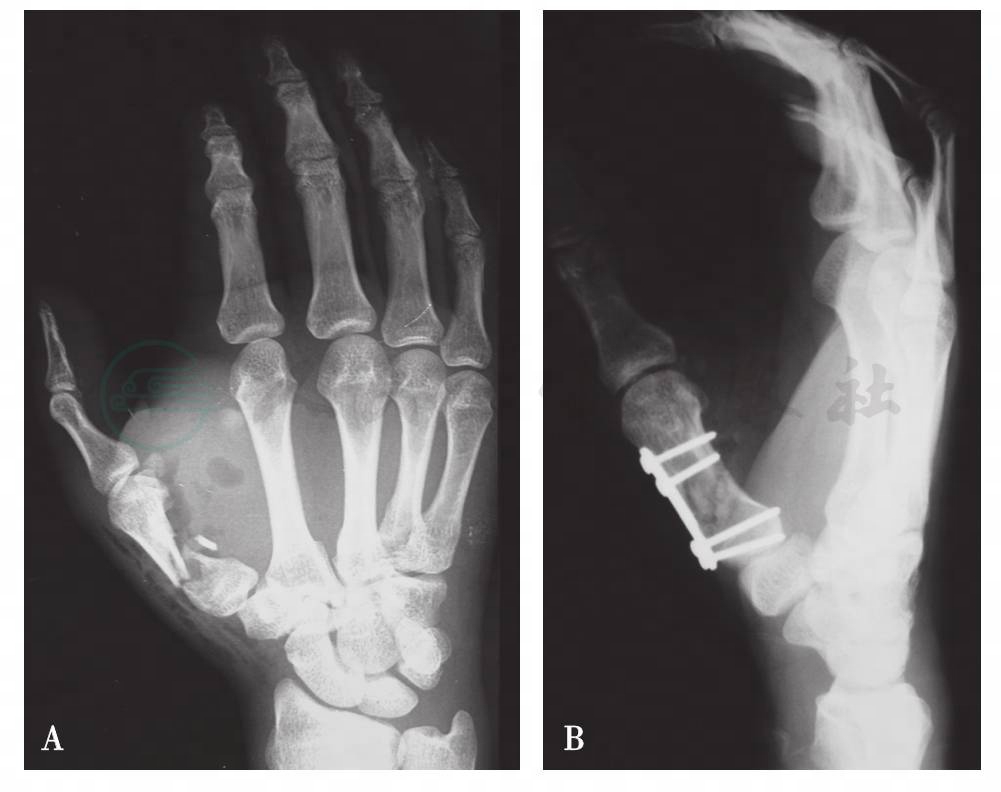

手部钢板的设计来源于大骨骼的治疗概念。但在手部,钢板占据空间大,容易影响肌腱、皮肤滑动,而且多需要二期取出,所以一直以来未受到广泛的临床应用。不过对一些伴有软组织缺损、关节内粉碎骨折、关节周围骨折、存在短缩旋转畸形的粉碎骨折及节段性缺损的掌指骨骨折较为适用。可以提供十分坚强的固定,保证较早地开始功能操练(图2)。有些特殊骨折也有了相应的特别设计的钢板。

图2第一掌骨骨折切开复位钢板内固定

A.术前X线片;B.术后X线片